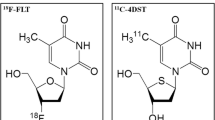

Positron emission tomography (PET) is now an indispensable modality for assessment of various tumors. The radiotracer 3′-deoxy-3′-[18F]fluorothymidine (FLT) has been investigated as a promising PET tracer for evaluating tumor proliferating activity in brain tumors [3–5]. A theoretic limitation of FLT as a radiotracer for the salvage pathway of DNA synthesis is that it is not incorporated into DNA because of the lack of a 3′-hydroxyl [6].

Toyohara et al. developed 4′-thiothymidine labeled with 11C at the methyl group (4′-[methyl-11C]-thiothymidine [4DST]), as a new candidate for cell proliferation imaging that is resistant to degradation by thymidine phosphorylase and is incorporated into DNA [7, 8]. A 11C-4DST PET pilot study of 6 patients with various brain tumors showed that 11C-4DST PET is feasible for brain tumor imaging and can be performed with acceptable dosimetry and pharmacologic safety at a suitable dose for adequate imaging [9]. In a mixed population of patients with newly diagnosed and recurrent gliomas, Toyota et al. has recently demonstrated that 4DST PET is feasible for evaluating cell proliferation [10]. These results indicate that 4DST has great potential for imaging cell proliferation.